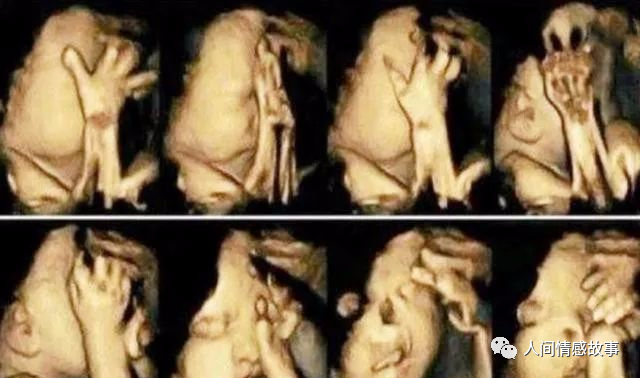

做B超看见胎儿不停做鬼脸,医生却说孩子不能要

小舒看着B超屏幕上孩子摆的各种姿势,觉得孩子在娘胎里就这么爱表现,以后肯定差不了。出去走了一圈之后,再回来做B超,宝宝果然很配合地露出了正脸。

小舒通过屏幕,看见肚子里的胎儿正在不停做鬼脸呢!正开心之时,医生却冷不丁地说一句:这孩子不能要,唇腭裂很明显,最好终止妊娠。